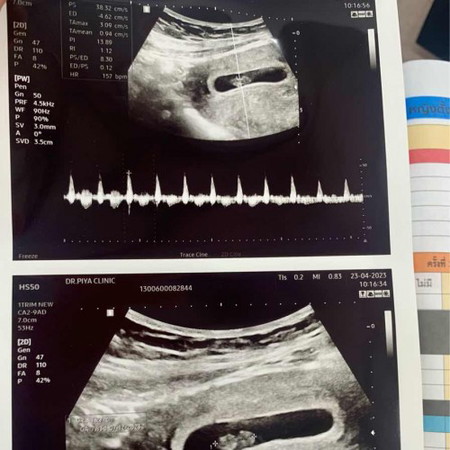

7week5day

เจอตัวน้องพร้อมเสียงหัวใจแล้วค่ะ☺️☺️☺️

1.27 เซนค่ะ😊